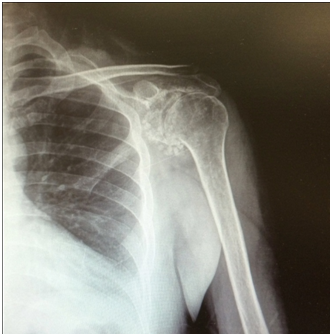

A 49years old male patient presented with a 3years history of progressive pain in the left shoulder, restricted range of movement and crepitation during the active movement of the left shoulder. He is a Non-smoker construction worker. He denied any trauma on the region and has no past medical history of interest for the pathology. He had no active movements above the head of the left shoulder after 40degrees of abduction. On the physical examination the active range of movements was limited, abduction 60º, adduction 40º, flexion 50º, extension 10º, internal and external rotation 20º, all of them were painful with crepitus during moment. We were able o identify rotator cuff sings of rupture and positive findings of subacromial impingement. He had a DASH test score of 52.5 being 0 the least dysfunctional score, and VAS score of 7/10 on a resting position and 10/10 during active range of movements. Plain radiographs of the left shoulder were taken identifying multiple calcification bodies within the articular space (Figure 1). An articular ultrasonography (USG) was ordered finding a complete rupture of the supraspinatus tendon no other tendon or labral abnormality (Figure 2). The differential diagnosis that should be considered are degenerative joint disease, osteochondritis dissecans, synovial sarcoma, chondrosarcoma, rheumatoid arthritis, pigmented villonodular synovitis and osteonecrosis of humeral head.3 The patient underwent a shoulder arthroscopy on a beach chair position under general balanced anesthesia. A standard anterior and posterior portals were used, finding a normal labrum tissue, a complete rupture of the supraspinatus tendon, multiple loose bodies and synovitis (Figure 3). The treatment consisted in loose bodies extraction, synovitis resection and the supraspinatus tendon rupture was reattached after debridement of the footprint with two 5.5mm Healix anchor (Mitek Sports Medicine; Raynham, MA) and two 3.5mm Push-Lock anchors (Arthrex; Naples, FL) using a modified Suture bridge technique. We had a positive confirmation from one of the loose bodies sent to the pathology department. The patient was discharged from the hospital the next day after the surgical procedure. A shoulder immobilizer with an abductor cushion had to be worn for 8 weeks. Starting physical therapy on week two with passive pendulum movements at home, and finally active movements and muscular strengthening at week 6. After 12weeks he started doing his normal life activities still no sport related activity. At the sixth post operatory month he had a final DASH Score of 18.2 and a resting VAS of 0/10 and during physical activity of 1/10. With active range of movement as followed abduction 100º, adduction 40º, flexion 120º, extension 25º, internal and external rotation 35º.

Figure 1 Left shoulder simple X-ray showing multiple intrarticular calcifications.